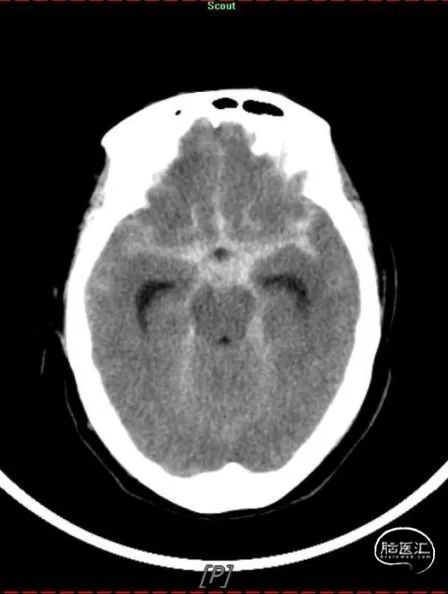

病史简介:患者女性,56岁,主因“发现右侧脑动脉瘤3月余”入院。查体神经系统阴性。3个多月前因“突发头痛、头晕3小时,神志不清2.5小时”伴有呼吸困难。被120送至我院急诊,予以行气管插管。急查CT提示“蛛网膜下腔出血”(图1)。头颅CTA提示“双侧颈内动脉C7段动脉瘤”(图2)。根据动脉瘤形状及CT蛛网膜下腔出血情况判断左侧脑动脉瘤为责任。遂急诊在全麻下行“DSA全脑血管造影术+支架辅助下左侧颈内动脉动脉瘤栓塞术”(图3)。手术经过顺利。术中同时发现右侧颈内动脉颈段冗长,迂曲严重,后交通动脉段亦见一动脉瘤,当时未做治疗。术后行“腰椎穿刺腰大池置管脑脊液引流术”。术后予护胃、营养神经、预防脑血管痉挛、脱水降颅压、抗感染、化痰、控制血压等对症治疗。术后康复出院。

图1

头颅CT示:动脉瘤介入栓塞术后改变,三脑室、两侧脑室轻度扩大。